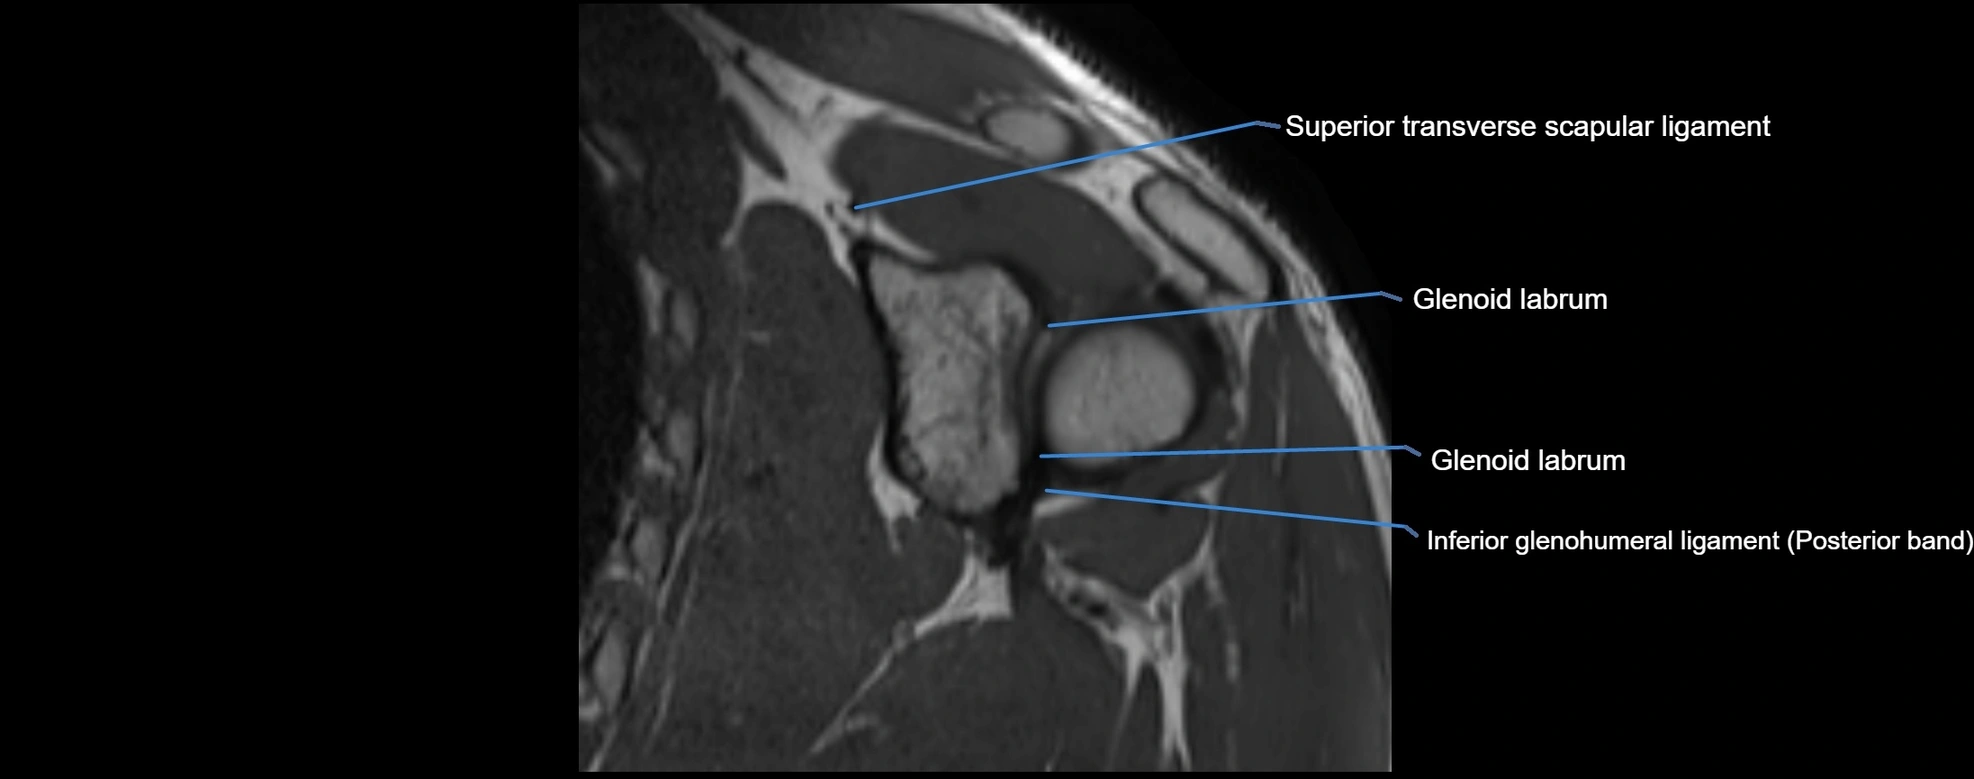

MRI images

image

CT image